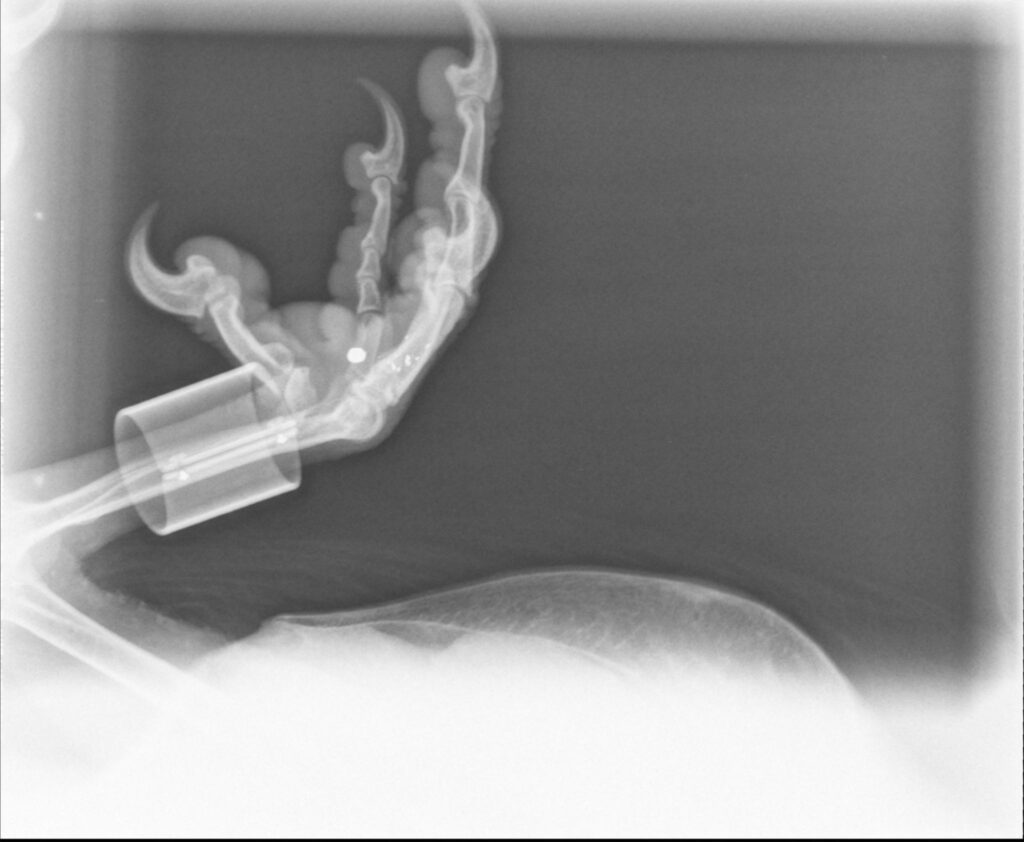

Examinations revealed a debilitated but alive bird weighing 4.8 kg. X-rays showed a cyst-encased lead pellet in the right foot and significant signs of arthritis. No recent trauma was detected. The vulture was transferred to the breeding centre the following day, where he rapidly improved, gaining 1 kg in just a few days.

The lead found in his foot: A troubling sign

Balthazar’s rescue highlights a serious concern: the lead pellet in his foot almost certainly originated from an old shooting. Even after many years, such embedded lead poses a toxicological threat (lead poisoning) and exemplifies the dangers faced by raptors.